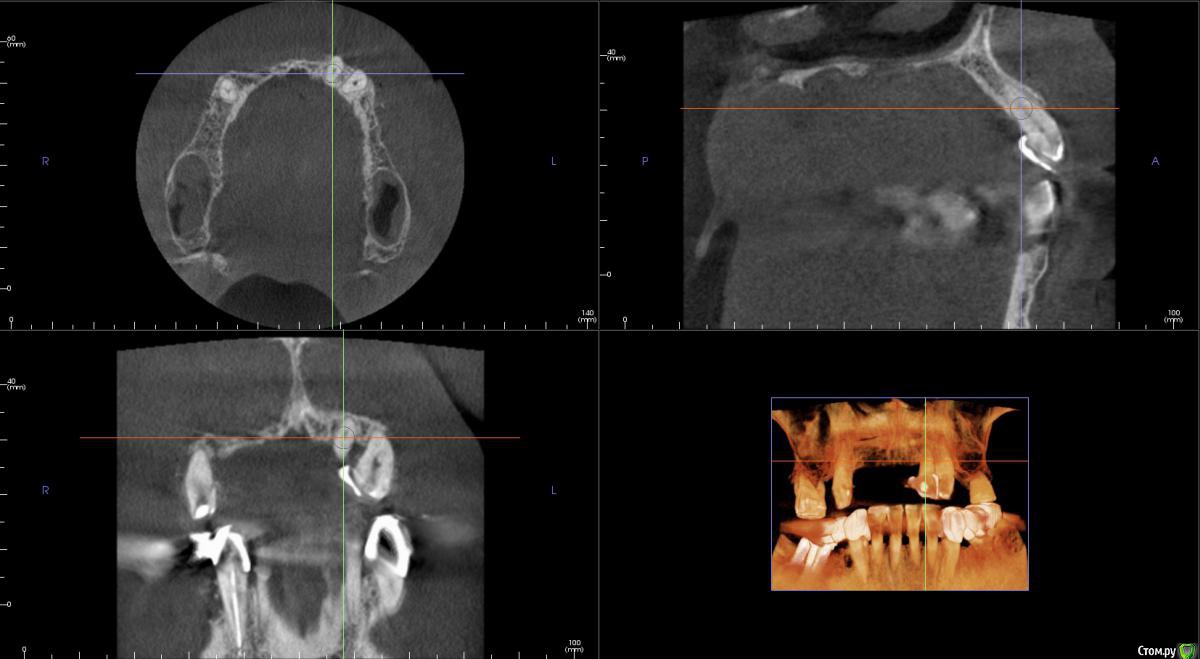

kamranchick Опубликовано 20 сентября, 2016 Поделиться Опубликовано 20 сентября, 2016 Интересует сторона 2. там хочу сделать соссидж, через несколько месяцев сделать закрытый синус и установить 2 винта в области 14 и 16, как вы думаете?и можно ли сделать конструкцию не брав во внимание фронтальный отдел? пациент финансово не тянет фронт Ссылка на комментарий

kamranchick Опубликовано 20 сентября, 2016 Автор Поделиться Опубликовано 20 сентября, 2016 Может убрать всё и на 4 ёх конструкцию предложить?думаю не получится, так как придется аугментировать и фронтальный отдел и боковой отдел чтобы по хорошему сделать все на 4, тем более я работаю на Осстем, а у нас мультиков в системе нет Ссылка на комментарий

колесников Опубликовано 20 сентября, 2016 Поделиться Опубликовано 20 сентября, 2016 думаю не получится, так как придется аугментировать и фронтальный отдел и боковой отдел чтобы по хорошему сделать все на 4, тем более я работаю на Осстем, а у нас мультиков в системе нетНе нужно там ничего аугментировать. Меняете корни на импланты. В обл премоляров так же есть объём по снимку. Иначе череда костных и мягкотканных пластик с неясным прогнозом. Пациент точно не потянет. У остема платформа 4.0 совместима с астровской 4.5-5.0. Можно у астры взять запчасти. Ссылка на комментарий